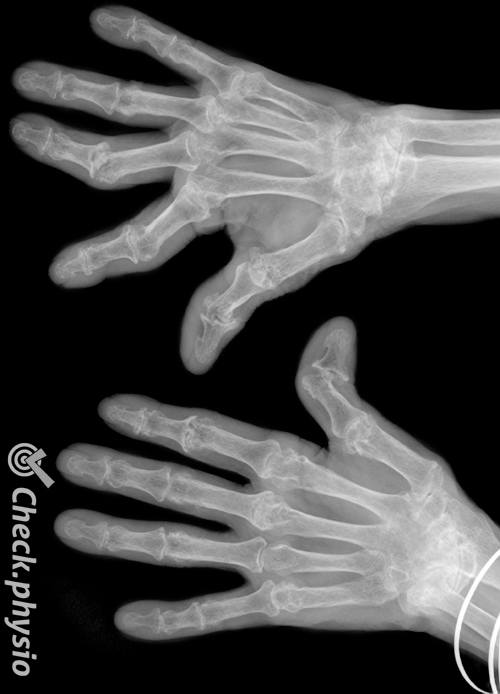

De viktigste kjennetegnene er smerte, stivhet og hevelse i leddene, for eksempel i hender, håndledd, ankler eller føtter. Det kan også forekomme plager i andre ledd som hofter, knær og skuldre.

Under huden kan det oppstå hevelser som skyldes betennelsen. Dette forekommer ofte ved albuer eller underarmer. Disse underhudshevelsene kalles revmaknuter eller nodulus rheumaticus. Uten behandling risikerer pasienten at leddene etter hvert blir deformerte. For eksempel kan det dannes store kuler i fingerledd på grunn av ekstra bendannelse.